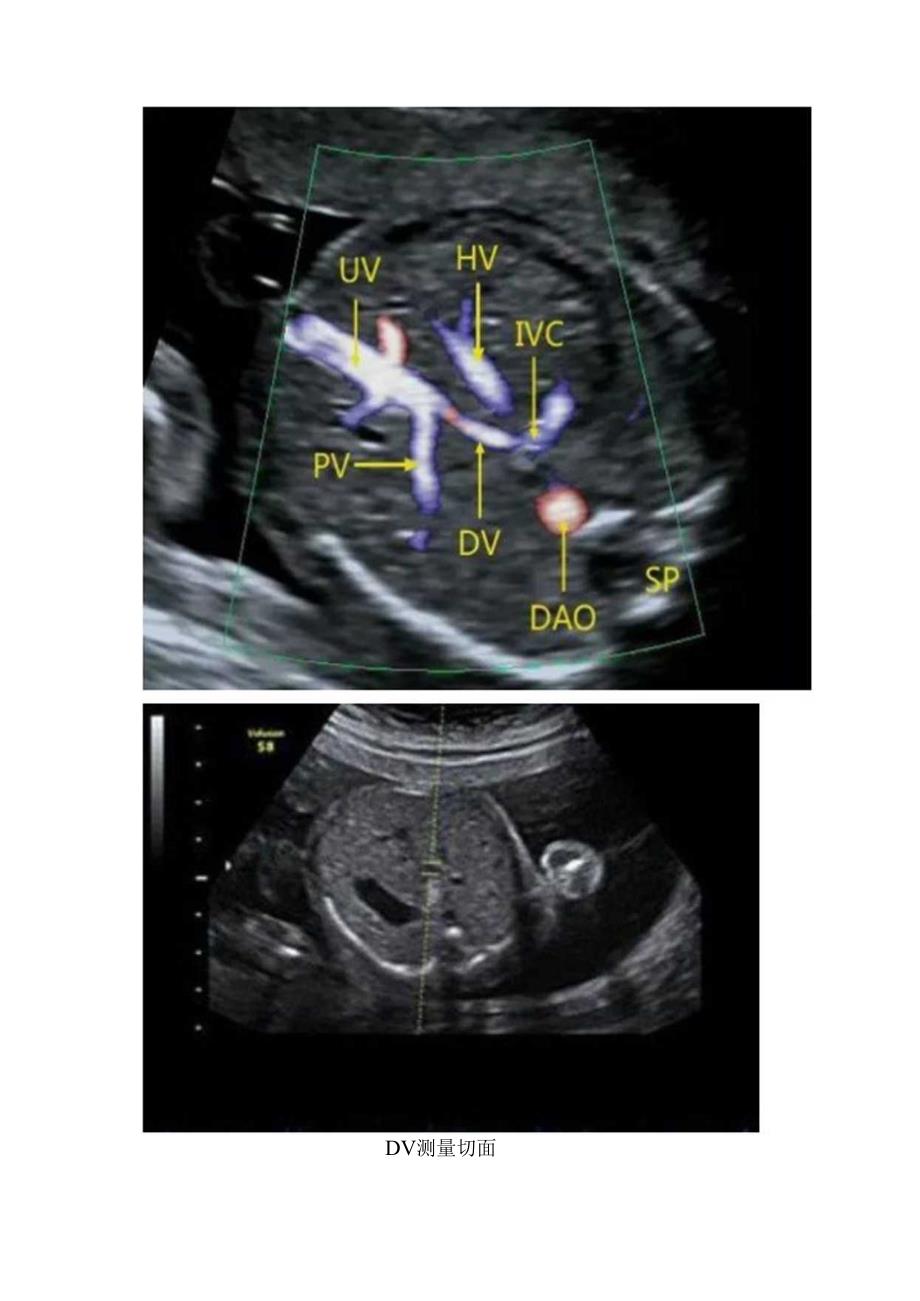

1、胎儿静脉导管血流频谱及临床意义静脉导管(ductusvenosus,DV)是胎儿时期3个特殊循环途径之一,是连接腹内脐静脉与下腔静脉进入心脏的特殊通道,来自胎盘的富氧血通过DV泵入下腔静脉。胎儿的生长发育与其密切相关。DV开口处有括约肌功能,调节血流阻力与压力。53%的脐静脉血经DV射入右心房,右心房与脐静脉之间的压力差和DV生理性狭窄形成DV的高速血流。出生后闭锁形成肝脏静脉韧带。一、静脉导管测量方法斜矢状切面显示出胎儿脐静脉腹腔段,用彩色血流追踪DV全程,适当调节彩色增益,色彩明亮处即为静脉导管,尽可能调节声束与血流方向平行,校正角度小于60,PIY获取连续而清晰的5个心动周期以上。DV测

2、量切面二、静脉导管频谱特点典型的DV多普勒频谱表现为三相波:心室收缩期波峰5、心室舒张早期波峰D和心房收缩期波谷a,正常情况下a波与S、D波在基线的同一方向,均为回心血流,持续整个心动周期。1.um1.m.正常DV频谱有报道认为10-14周正常胎儿的静脉导管血流频谱中存在着1.5%、9%的生理性零或反向a波。反向a波的出现,可能是由于在静脉导管的近心段,静脉导管、肝静脉和下腔静脉位置邻近,取样容积同时包括了三者血流,频谱混合,后二者的房收缩波会被误认为是静脉导管内的反向a波,调整取样容积的位置,尽量使其位于静脉导管中段,避免发生混淆。另外较高的壁漉波也会把流速较低的正向a波滤掉,使a波表现为零,通过降低壁滤波可避免此现象的发生,正常胎儿DV的SV随胎龄增长而逐渐升高,aV随胎龄增长而升高更加明显,PIJH和S/a则随胎龄的增加而减低。胎儿DV的检测时间5min.三、静脉导管异常的临床意义a波缺失或反向常见几种情况:非整倍体染色体异常、心脏缺陷、宫内生长受限、11s及胎儿心脏功能受损等情况,晚孕期a波倒置是距离胎儿宫内死亡最近的一个血流动力学参数。DV缺失是一种罕见的血管异常,伴发其他先天性异常的风险增加。DVa波缺失、反向